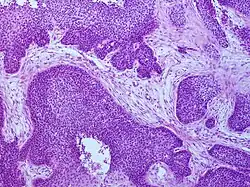

Squamous-cell carcinoma

Main histopathology features of squamous-cell carcinoma

Biopsy of a highly differentiated squamous-cell carcinoma of the mouth. Typical squamous-cell carcinoma cells are large with abundant eosinophilic cytoplasm and large, often vesicular, nuclei.[14] Haematoxylin & eosin stain